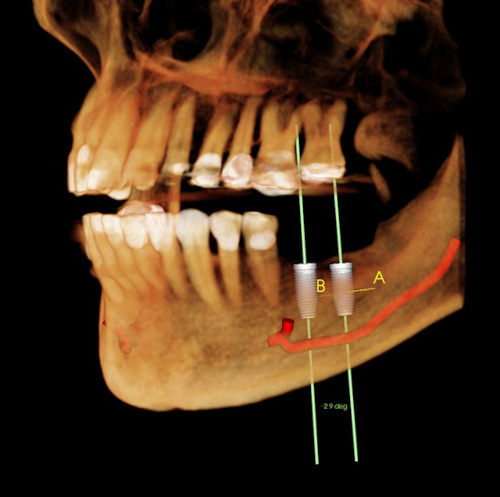

Damage to the inferior dental nerve (NDI)

The dental nerve runs through the lower jaw. When placing a traditional implant, there is a risk of damage to this nerve when drilling with a large diameter. The results can be very inconvenient for the patient. Paralysis or loss of feeling on one side of the face, lips, and teeth. Sometimes the nerve may simply have been affected without being damaged. In this case, the loss of feeling is temporary.